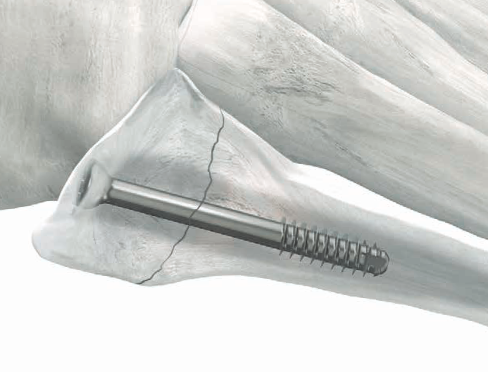

Intramedullary screw

Technique

Entry point

- 5th metatarsal is not straight

- high and medial to get straight shot

- avoids plantar insertion peroneus brevis

- screw diameter 3.5 / 4.5 / 5.5 / 6.5

- screw threads must be distal to fracture site to allow compression